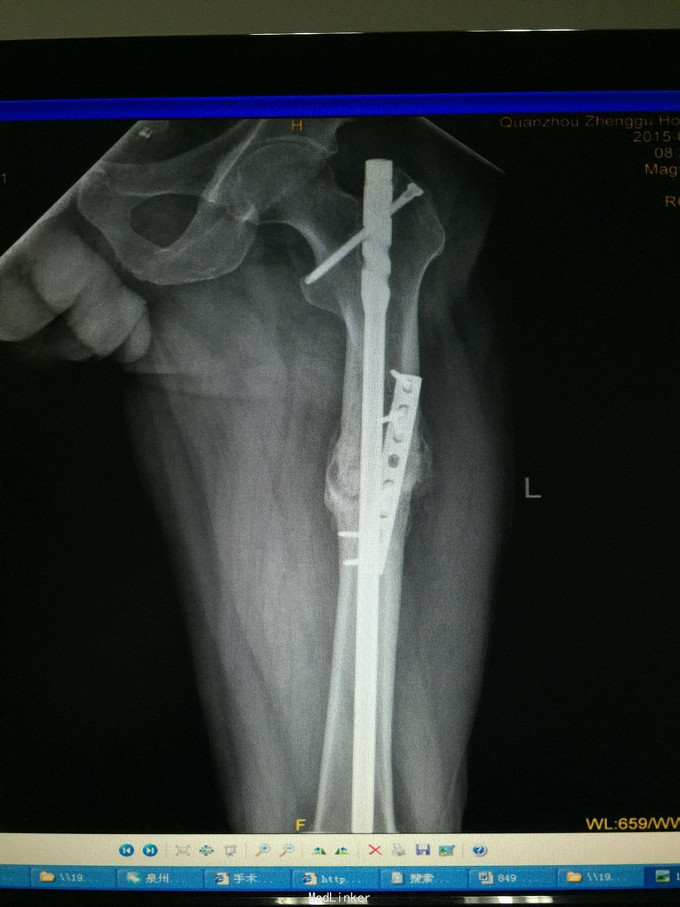

左股骨中上段骨折术后骨不连

诊断:左股骨中上段骨折术后骨不连 处理:左股骨骨折术后骨不连断端清理+防旋钢板内固定+取髂骨植骨术

术后半年 讨论 考虑股骨中上段骨折 应力集中 近段一枚螺钉稳定性不够?